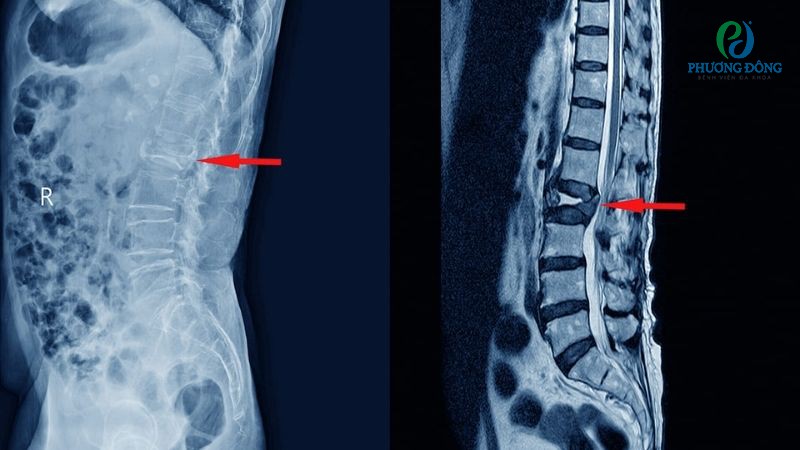

Bố của tôi đau lưng do thoái hóa đốt sống và ông có thói quen thích nằm võng. Tuy nhiên tôi được biết đau lưng nằm võng không tốt. Vậy xin hỏi đau lưng có nên nằm võng?